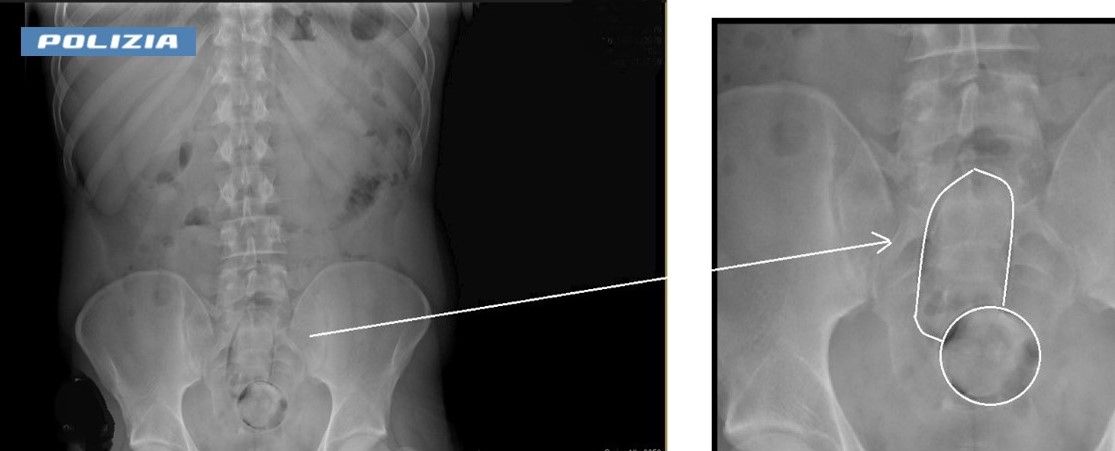

Dall’esame radiologico è emerso che nell’addome del sospettato vi erano due corpi estranei, risultati essere due palloncini contenenti rispettivamente 50 e 100 grammi di hashish.